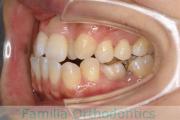

No.22V-449

- 主な症状:

- 上顎前突

- その他の症状:

- 叢生

- 年齢:

- 14歳

- 性別:

- 男性

- 抜歯部位

- 上:

- 44

- 下:

- 8448

- 主な使用装置:

- FEA

- 治療にかかった費用:

- 87万円

歯並びをきれいにしたいということで来院されました。上下左右から小臼歯を抜歯して、マルチブラケット法を行っています。2年弱、25回程度の通院が必要でした。

かなり強い叢生(でこぼこ、凹凸、ガタガタ)ですので、保定をしっかりしないと後戻りのリスクがあります。

- ≫治療前

-